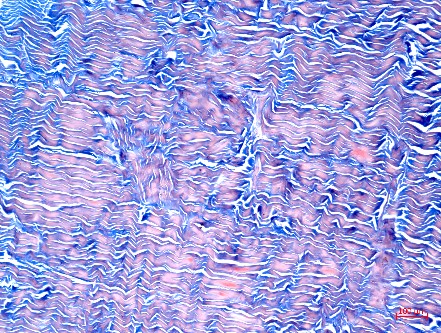

2、Masson染色实验结果(兔肌腱、大鼠股骨、大鼠皮肤、举例)

Masson染色实验解读:图片结果呈现胶原纤维蓝色,肌纤维红色,细胞核紫蓝色。